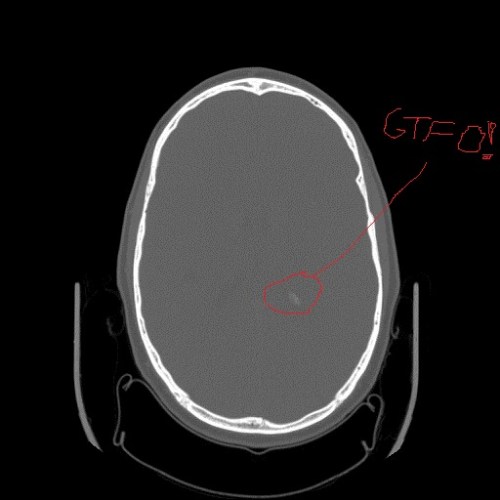

Stomach-Churning Rating: 1/10; a medical imaging scan of my disintegrating body, and a cartoon of surgery.